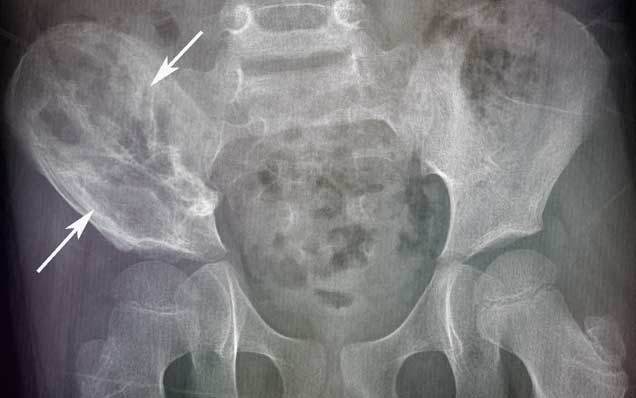

Наиболее частые локализации саркомы Юинга:

- кости таза,

Рентгенологические признаки саркомы Юинга:

- поражение кости без четких границ, так называемый симптом «изъеденная молью», чаще распространяется по костномозговому каналу;

- «луковичный периостит» – многослойный периостит, сочетающийся с игольчатым;

- наличие мягкотканного компонента однородной структуры;

- в 5% случаев встречается патологический перелом.